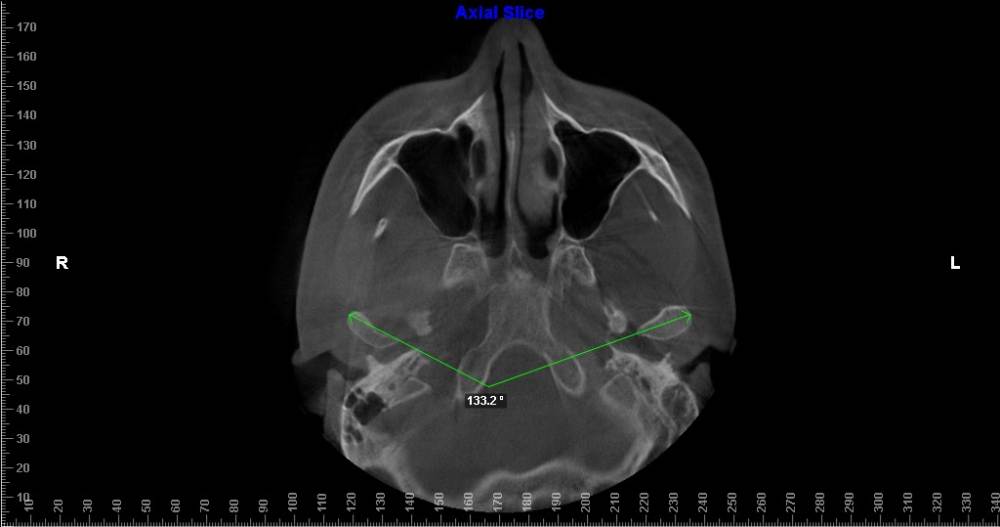

В общем нашел  врача-ортодонт, сделал снимок ортодонт-3 в одном центре и вот сегодня со снимками посетил врача.  Врач сказал, что только в комбинации с челюстной лицевой операцией можно, что то исправить. Подскажите, есть смысл идти к другому специалисту на консультацию что бы все таки без операции? ( Операцию делать не хочу)

угол между суставными головками.jpg